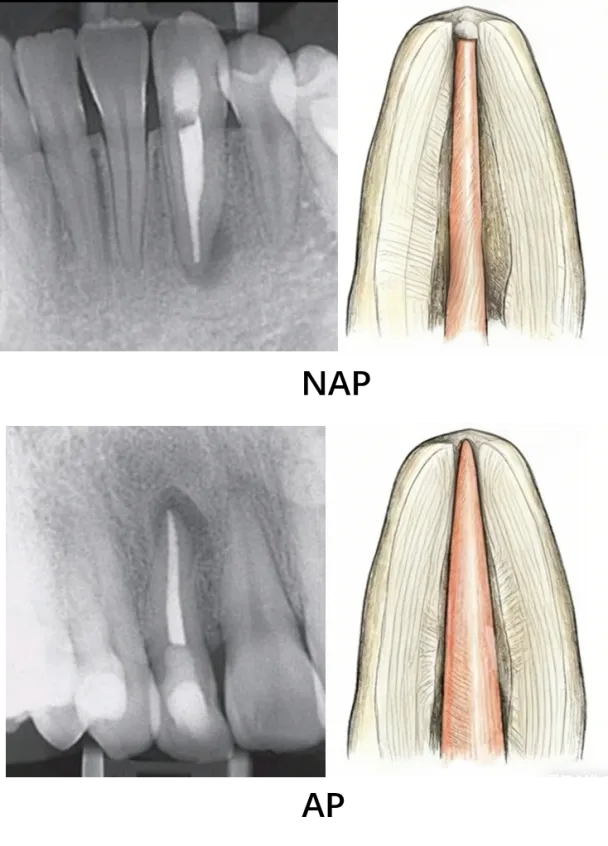

在应用根尖通畅时需严格规范操作,避免通畅演变为超预备。超预备是指预备过程中使用 #20 及以上大号锉强行拉开根尖孔,破坏根尖狭窄结构,而根尖通畅则是用小号锉被动疏通,完整保留根尖狭窄原始形态与大小。

图3 避免根尖通畅成为超预备